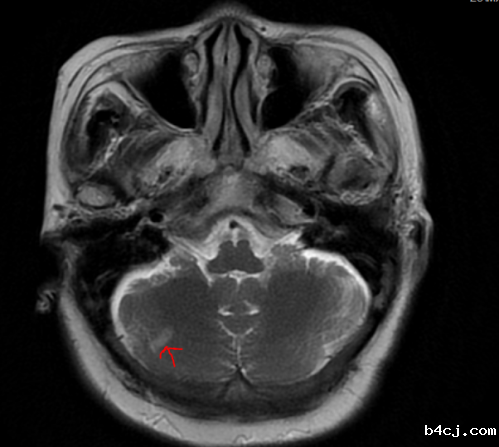

刘平主任接诊后仔细询问了病史,认真查体,发现老太太除了有眩晕之外,以前还有头痛病史,这次发作以后眩晕持续时间长,复位多次无明显减轻,在进行了前庭功能相关检查后,发现并不符合耳石症的诊断,考虑中枢性位置性眩晕的可能性大,立即安排患者进行脑部MRI检查,核磁共振检查结果报右侧小脑急性梗死(小面积),需要住院治疗,在神经内科经过近1周左右的治疗后,老人家眩晕消失,已康复出院。

但临床上除了耳石症以外,脑部病变也会表现为反复发作的位置性眩晕,一旦多次复位效果不好,首先要考虑中枢性位置性眩晕,其症状和耳石症相似,可以表现为体位变动的眩晕。中枢性位置性眩晕多发生于第四脑室背外侧,小脑等部位,可表现为脑梗死或者小脑出血,需要通过核磁共振明确诊断。治疗主要根据核磁共振结果采取相应药物治疗,越早发现,越早治疗,愈后越好。

红色箭头部分为梗死灶